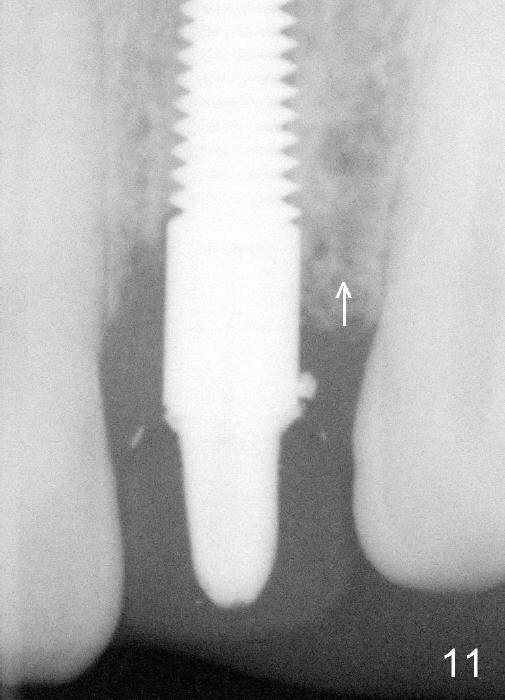

Fig.2: A gutta percha inserted to the buccal fistula (Fig.1 >) shows a mesial defect ( <). *: periapical radiolucency. Fig.3. Immediately post implantation (4x20 mm). Fig.11: Four months postop. Crest bone appears to have mild resorption (arrow).